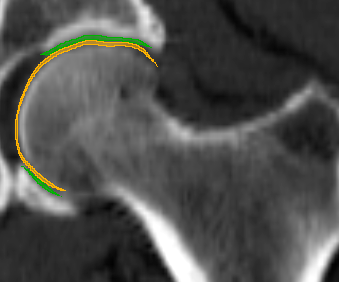

We have qualitatively verified that the articulating surfaces in all the ten HJs are detected correctly regardless of their anatomical variance using visual inspection of overlays as shown in Fig. 4. As desired, we observe a high degree of congruence between the opposing joint surfaces, meaning no gaps or overlaps in the cartilage-cartilage interface. Moreover, we observe a smooth transition towards the bone geometries as expected from the correct anatomy. The parameter values used to generate the cartilage from Fig. 5(a). The free parameters are the neighbourhood-size used to estimate the curvature of the bone (𝒩𝒩\mathcal{N}); the minimum and maximum curvature in the cartilage region (κmin,κmaxsubscript𝜅subscript𝜅\kappa_{\min},\kappa_{\max}; Eq. (2)); the distance parameter in mm𝑚𝑚mm (δ𝛿\delta; Eq. 1); and the number of times the outer boundary should be trimmed (Ntrimsubscript𝑁𝑡𝑟𝑖𝑚N_{trim}). Here, the curvature based parameters (𝒩,κmin,κmax)\mathcal{N},\kappa_{\min},\kappa_{\max}) are only used for the femur. See supplementary material for more visual comparisons.

Fig. 4 visualizes the von Mises stress pattern on the pelvic cartilage for one HJ. More are shown in the supplementary material. We have verified that no spurious stress peaks appear and that stress values change gradually and smoothly across the cartilage. Further, the high-stress areas are located in the up-direction, as we expect from the applied displacements. The stress values and patterns are not to be confused with those from a real stance. They only serve as a verification test of simulation properties. For such a simulation, we require ligaments and muscles to stabilize the girdle and a correction from sublime pose bias.

Refer to caption

(a) Von Mises stress.

(b) CT scan overlay.

Figure 4: The von Mises stress patterns ((a)) and the generated cartilage imposed on the CT scan from which the bone was extracted ((b)). Notice the high level of congruence in the cartilage-bone interfaces and cartilage-cartilage interface.